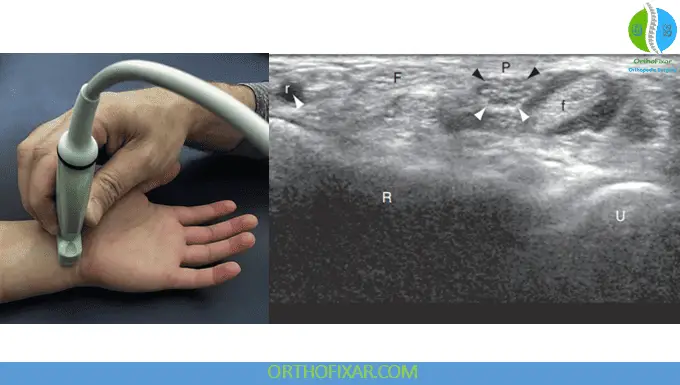

Scanning Technique: Begin by placing the transducer along the proximal carpal tunnel in the short axis. This positioning allows visualization of multiple structures simultaneously, including the median nerve, flexor carpi radialis, flexor digitorum superficialis, and the tendons of the flexor digitorum profundus. The radius and ulna provide additional bony landmarks for orientation.

Dynamic Wrist Ultrasound evaluation enhances diagnostic accuracy by having the patient perform finger flexion and extension movements. This technique reveals tendon gliding patterns and can identify adhesions or mechanical restrictions within the carpal tunnel.

The median nerve appears as a “honeycomb” pattern when viewed in short axis, displaying hypoechoic fascicles surrounded by hyperechoic epineurial connective tissue. This appearance helps differentiate the nerve from surrounding tendinous structures.

Pathological Assessment: Normal median nerve cross-sectional area at the wrist measures approximately 9 mm², increasing to 14 mm² in patients with carpal tunnel syndrome. Measurements should be standardized at the level of the distal radius or pisiform to ensure reliability and reproducibility.